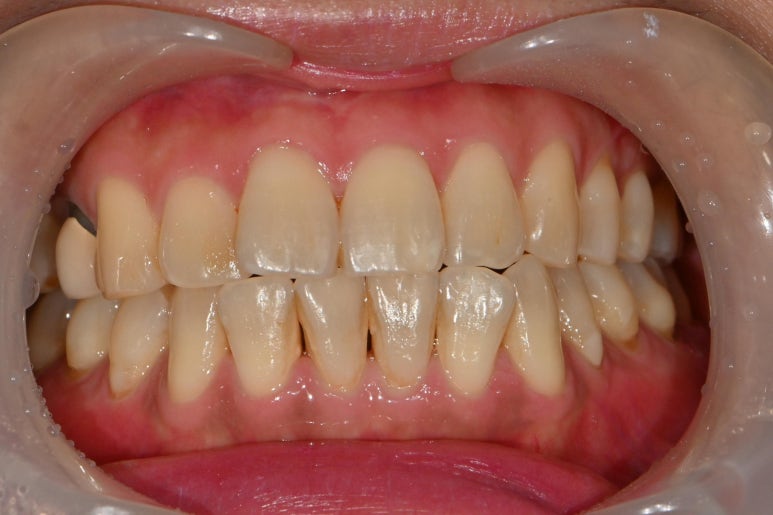

오늘 소개할 증례는 치경부 마모증입니다.

치경부 마모증이란 치아의 목 부분이 마모된다는 것입니다.

환자분은 찬물 마실때나 양치를 할때

' 시리다 ' 라는 주소로 내원하신 분이십니다.

치경부 마모증의 원인은 씹는힘이 강하거나,

양치를 너무 강하게 하거나

치열이 고르지 않을때 많이 생깁니다.